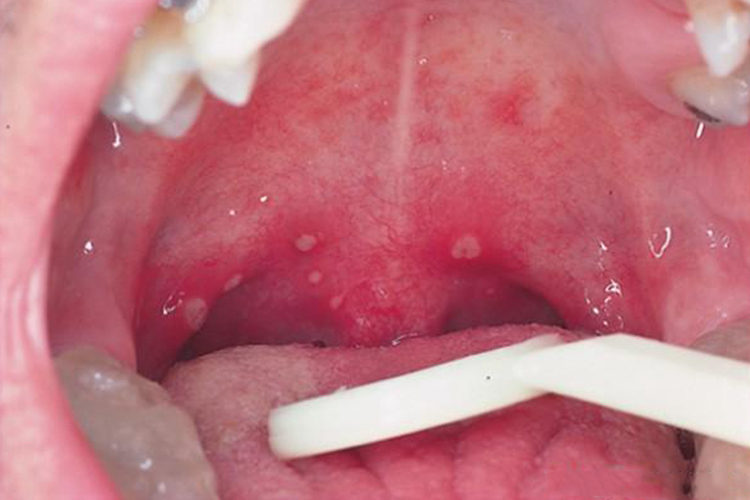

手足口病可在口腔咽峡部出现红色斑疹,会很快发展为2-4mm的水疱,疱壁薄且疱液清亮,周围会绕以红晕。水疱溃破后可形成灰白色糜烂面或浅溃疡。